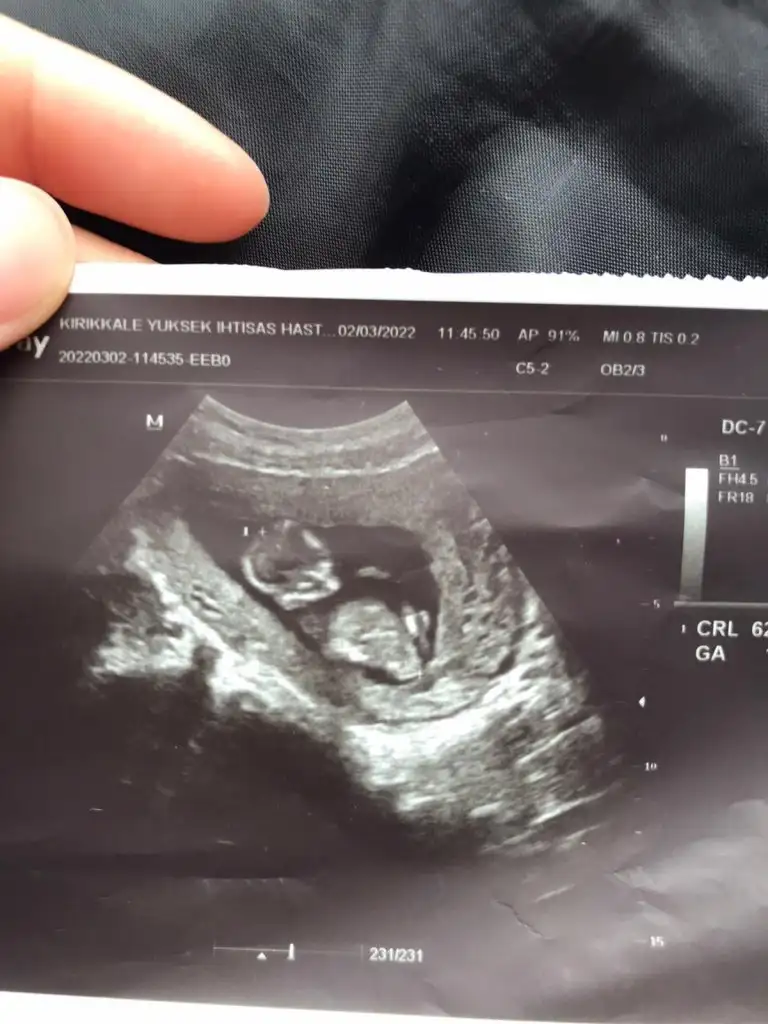

11+6 günlük karından bakıldı